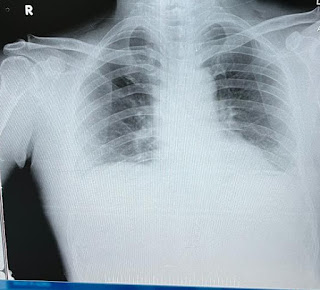

☆RESPIRATORY SYSTEM:

•trachea central in position

•Normal vesicular breath sounds heard

•BAE ++